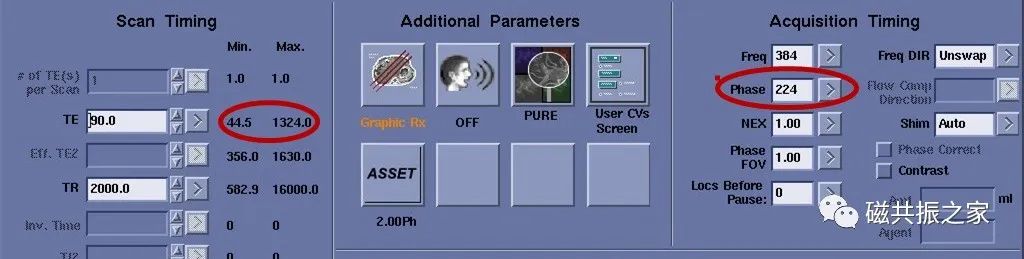

带宽

图1,BW为31.25时,扫描时间为1:53,图2,BW为15.63时,扫描时间为2:41。其原因是带宽减小了,其驻点时间增加了,如果注意观察其回波时间会发现回波时间延长了。带宽减小了虽然信噪比增加了,但ESP的延长会导致图像模糊加重。